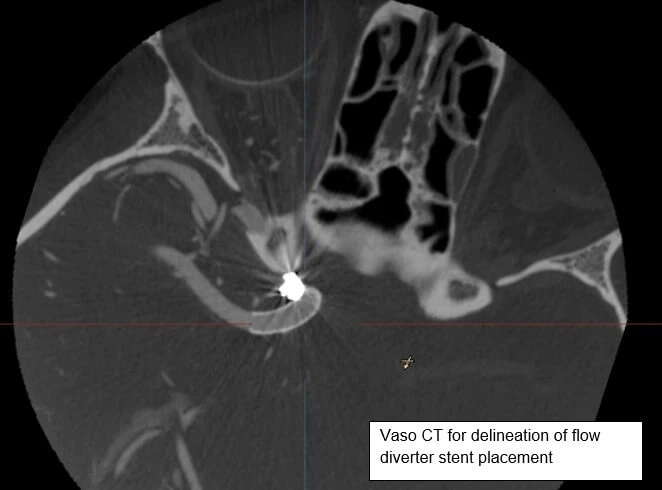

Vaso CT

Vaso-CT ( of Philips Medical system) is a more higher resolution version of CBCT. During a Vaso-CT biplane angiography, a contrast agent is injected into the patient's bloodstream to highlight the blood vessels.

The additional advantage of Vaso-CT is it provides detailed information of the various devices placed inside the brain blood vessels including stents, flow diverter devices, intrasccular devices like Web.

Specific details pertaining to device functioning like adequacy of device placement, impingement on normal brain blood vessels and adequate opening of the device are exclusively delineated using this particular software.